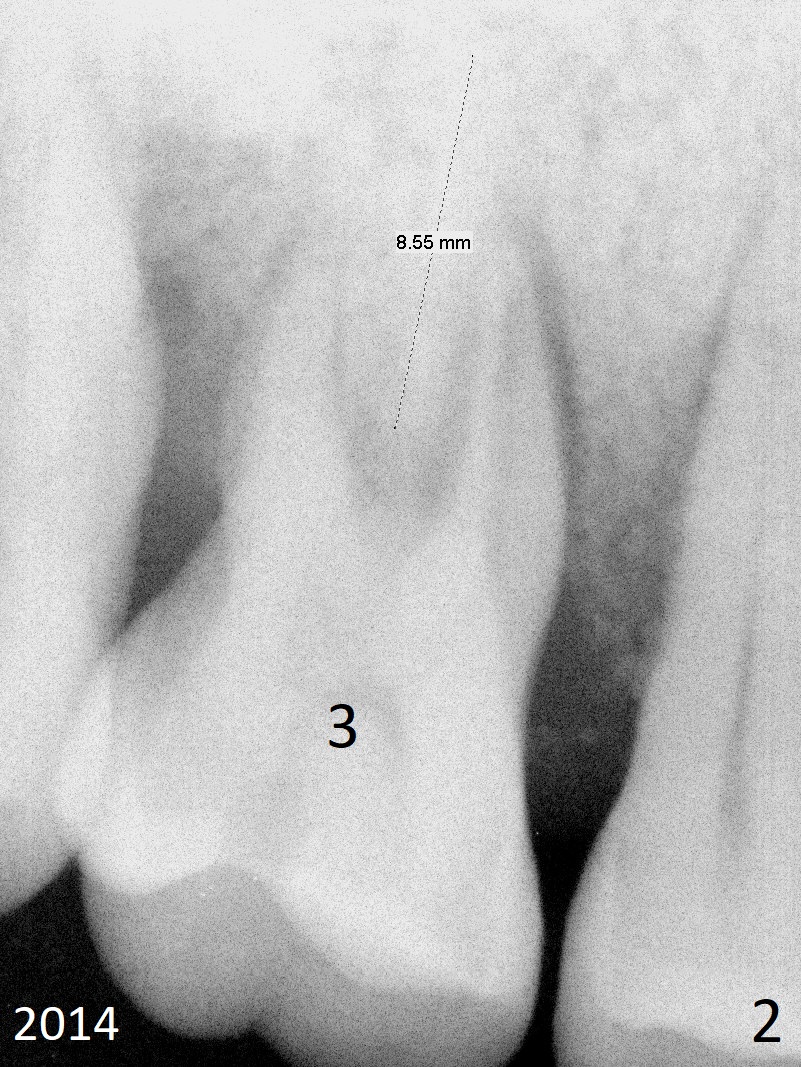

A 48-year-old woman has generalized moderate localized (#3,14) advanced periodontitis (Fig.1). The edentulous area at #6 has been restored. Now the tooth #3 has mobility III (Fig.2), while #14 has exfoliated (Fig.3,4). If the tooth #3 is symptomatic, extract it for immediate implant. Otherwise use Magic Split to initiate access and osteotomy expansion, followed by Magic Expanders (3.0 and 3.8 mm) or Magic Sinus Lifter. Insert Tatum tapered taps. If the gingiva is excessively long, switch to UF implant for mill abutment.

In fact the tooth #3 is not exfoliated. Take PA preop for height measurement. If the bone height is less than 8 mm, use IS drills with shorter stoppers. Use Bone Scalpels and Bone Blades to start osteotomy, followed by Rounded Tapered osteotomes. Prepare the implant kit if the bone turns out to be dense. Take photos and PA for #6.